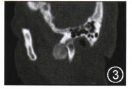

MRI:右颞下领关节及颅底可见形态不规则结节状,T1稍长、T2不均匀信号影,间隙增宽,病变边缘光滑,与周围组织界限清晰,右侧翼内、外肌萎缩。增强扫描病变内可见不均质中等程度强化。提示:右颞下颌关节良性肿瘤(图4~6)。